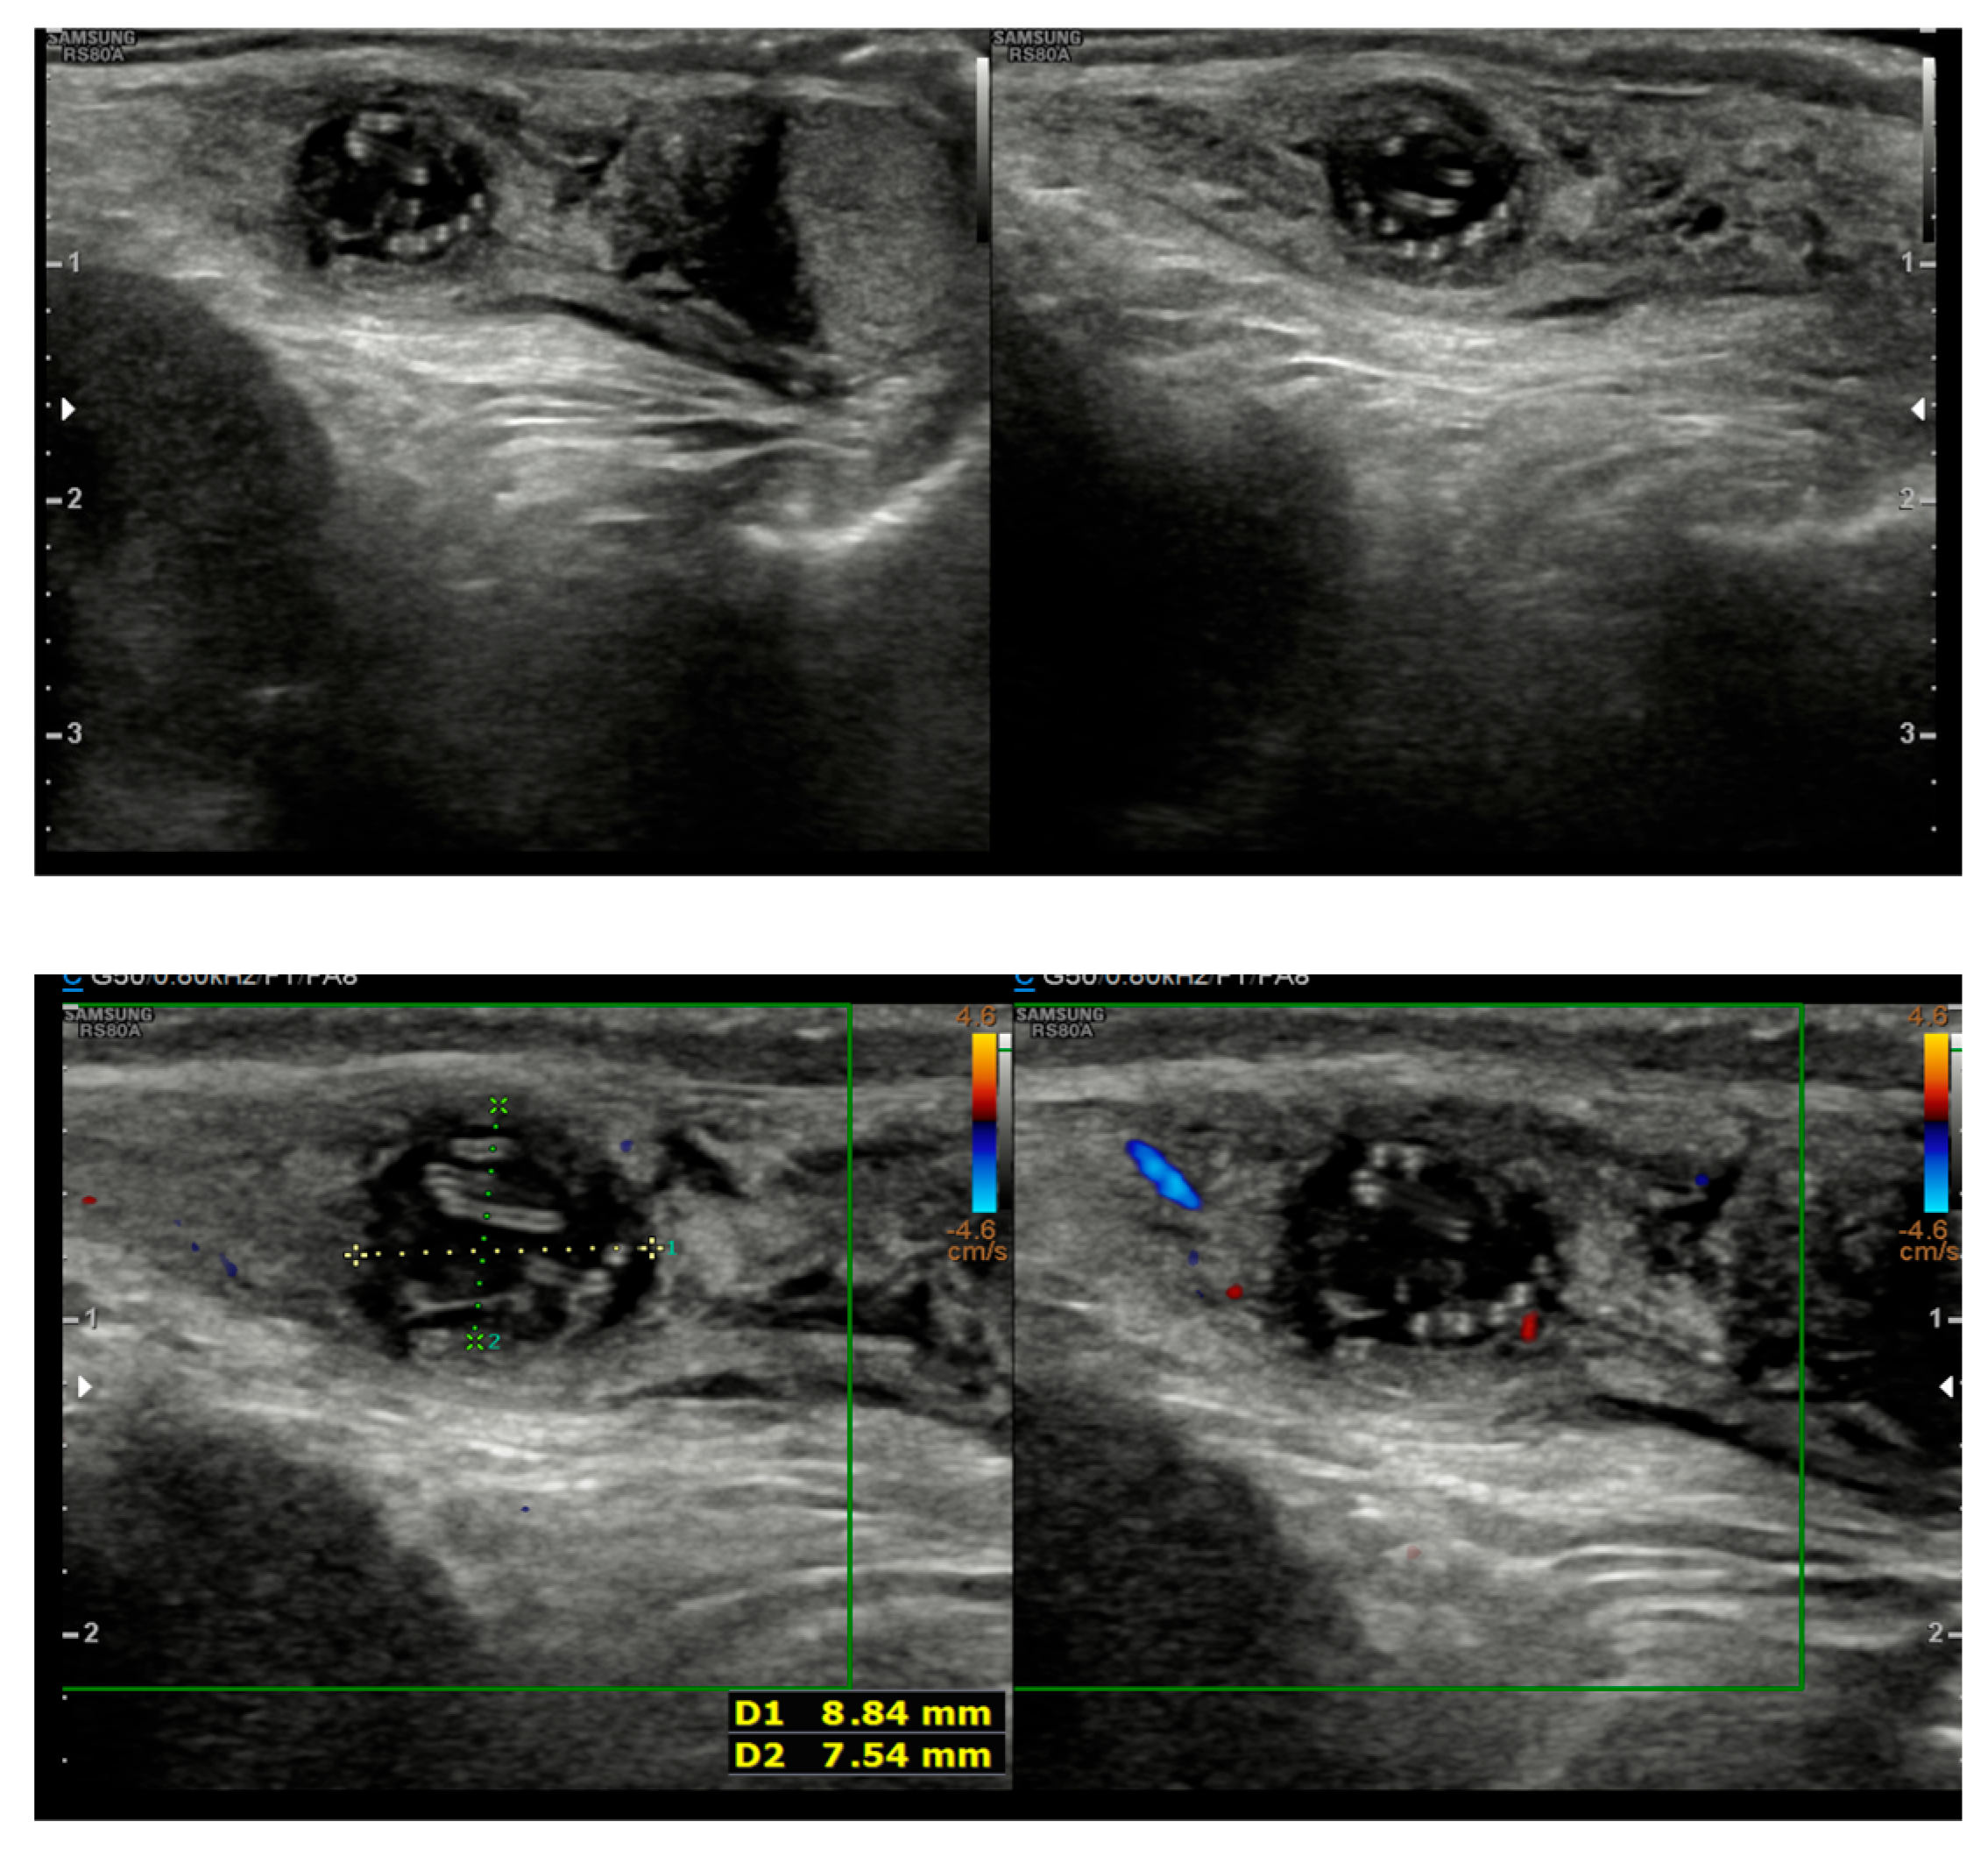

2. Case Presentation